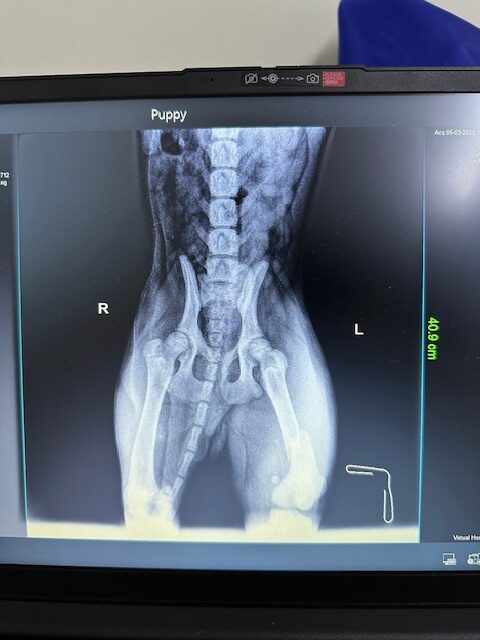

Vali was hit by a car on the airport road . He had one broken front leg, one broken back leg and one broken pelvis. He’s very scared. He’s good with other dogs. DOB: 10/10/2024